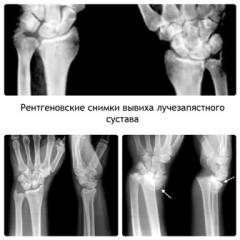

Диагностика вывиха лучезапястного сустава

Диагностика вывиха лучезапястного сустава обычно не вызывает трудностей, но необходима дифференциальная диагностика с переломами лучевой кости, так как клинические проявления могут быть схожи. Для этого используются рентгенологические данные.

Методы диагностики вывиха лучезапястного сустава:

- Сбор анамнеза. Травма, связанная с падением, резким движением или ударом, может указывать на вывих.

- Физикальное исследование. Отечность и деформация пораженного сустава по сравнению со здоровой рукой. Ограничены активные и пассивные движения. При пальпации суставной конец может быть не прощупываем или находиться не на своем месте.

- Рентгенологическое исследование подтверждает диагноз вывиха, определяет расположение вывихнутых суставных концов и исключает перелом.

- МРТ оценивает состояние и степень повреждения мягких тканей.